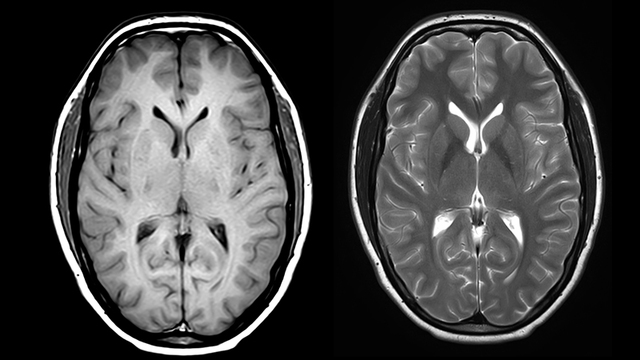

Se le realizaron exámenes paraclínicos de ingreso, los cuales mostraron glucometría 272 mg/ dl, y Hb Glicosilada 15,8% . Además se le realizó RM de encéfalo, en la cuál se evidenció lesión que restringía la difusión, visible en FLAIR y T2. Imagen hiperintensa en T1.